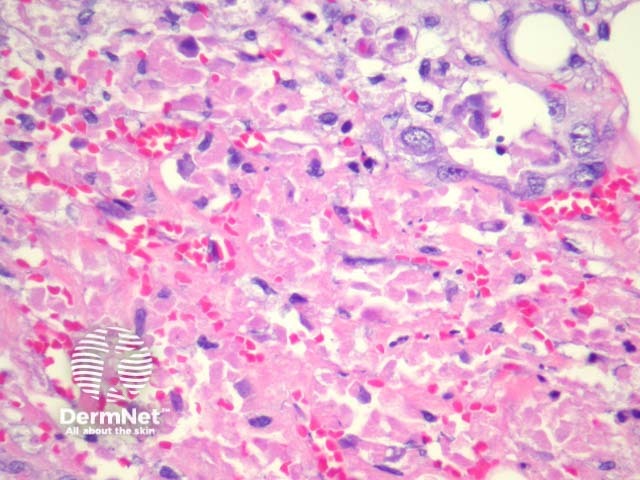

In sebaceous carcinoma, the tumour is generally dermally based with invasion into subcutis (figure 1) and native structures. Pagetoid invasion of the overlying epidermis may be seen. The tumour cells are basaloid with foci of sebocytic differentiation. Sebocytes are large cells with a multivacuolated clear cytoplasm (figure 2). Necrosis is common (figure 3, 4).

Figure 3

Figure 4